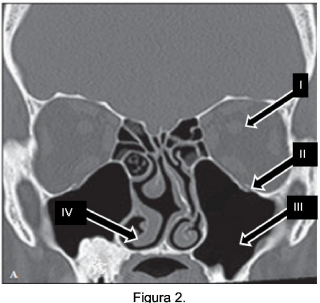

A tomografia computadorizada (TC) tem papel fundamental no estudo do aparelho auditivo, uma vez que, através dela podem ser avaliadas estruturas não visualizadas no exame com otoscópio. Em situações clínicas diversas, o diagnóstico, por meio desse exame, mostra-se limitado, sendo fundamental o exame de imagem associado às reformatações digitais. Observe a figura 1 para responder a questão.

Com relação às estruturas anatômicas apontadas na Figura 1 é correto afirmar.

Com relação à Figura 1 é correto afirmar: